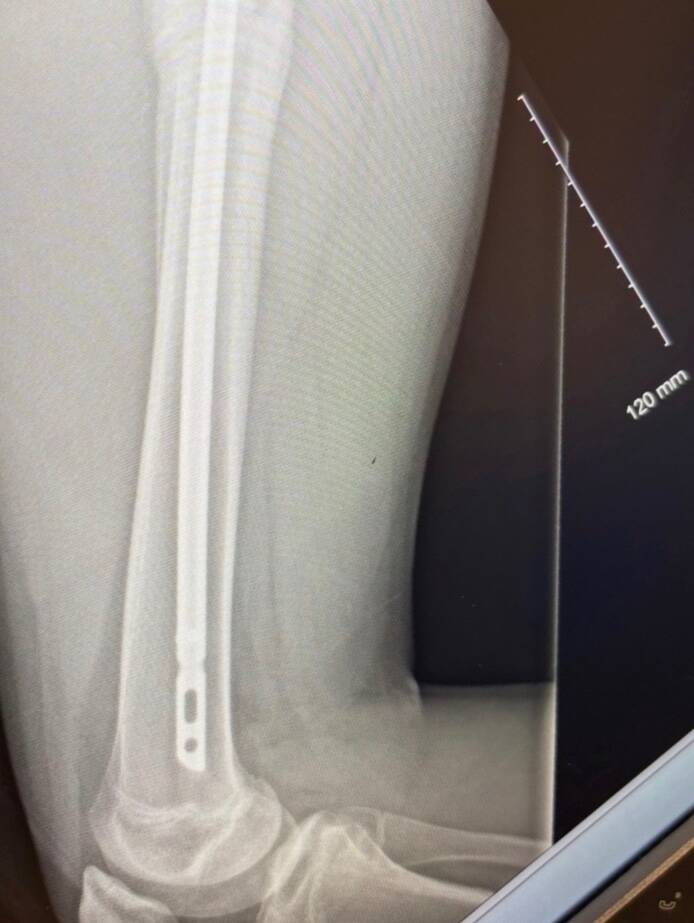

An X-ray shows a steel rod that was placed in Talon Scinocca's broken right femur to fix the damage.(Submitted)

Talon had a 90-minute surgery the next morning, with a steel rod inserted into the hollow bone to stabilize it.

If it had broken in multiple spots, the surgery would have been much more involved. Instead, Scinocca left hospital the next day on crutches, which would be a familiar accessory to him for nearly two months.

The six-foot-two, 165-pound teenager never wore a brace or cast.